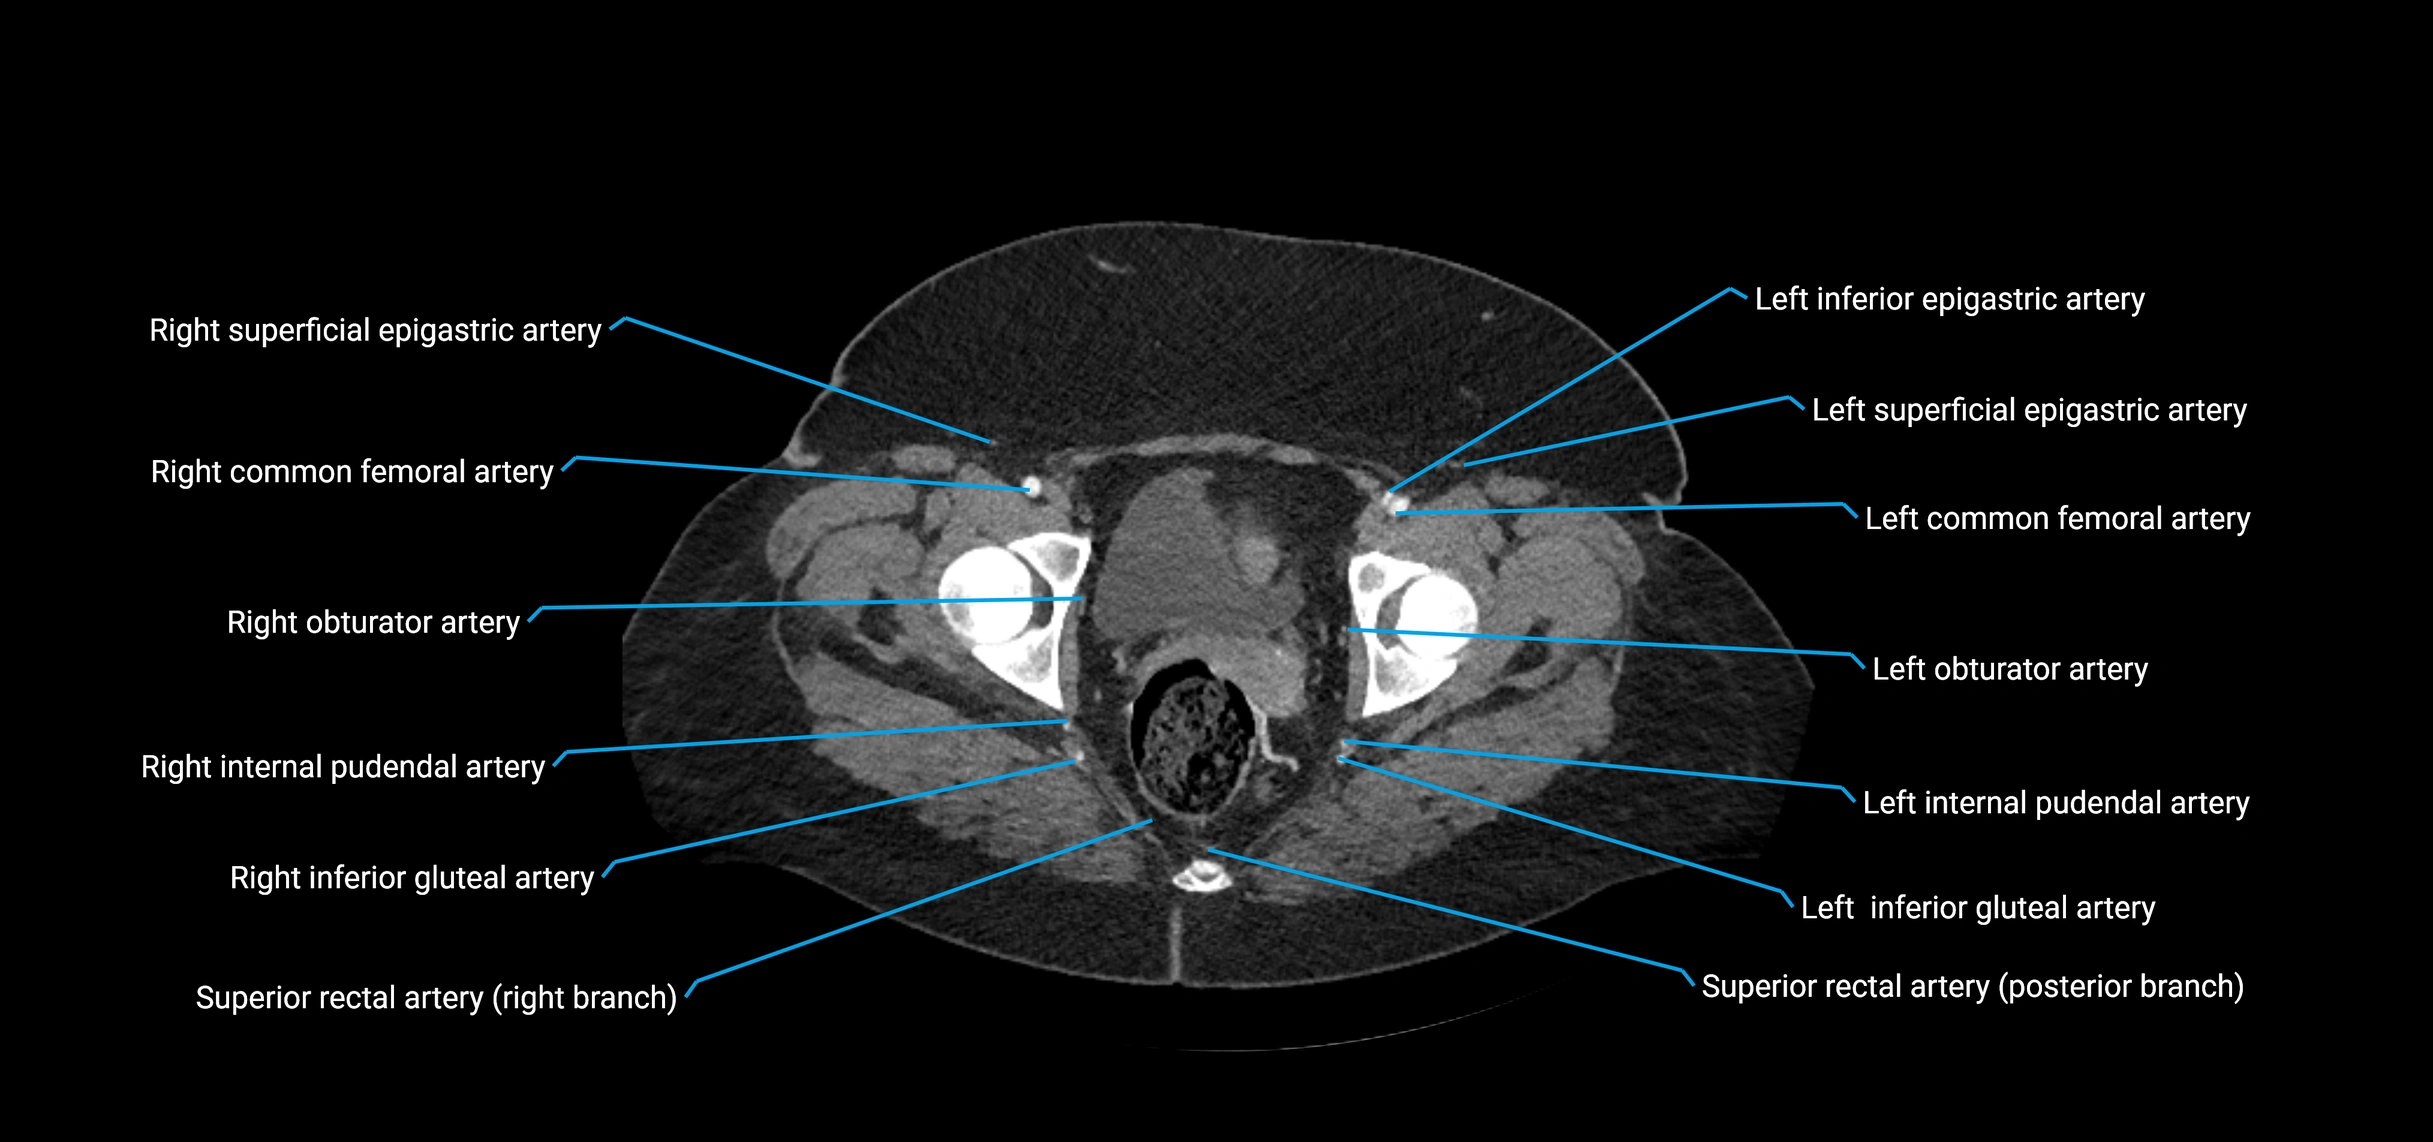

CT images

image

Contrast-enhanced CT (CTA):

• Gold standard for abdominal aortic imaging

• Provides excellent detail of lumen, wall, aneurysm, thrombus, and branch vessels

• Multiplanar and 3D reconstructions help in aneurysm measurement, stent graft planning, and dissection evaluation